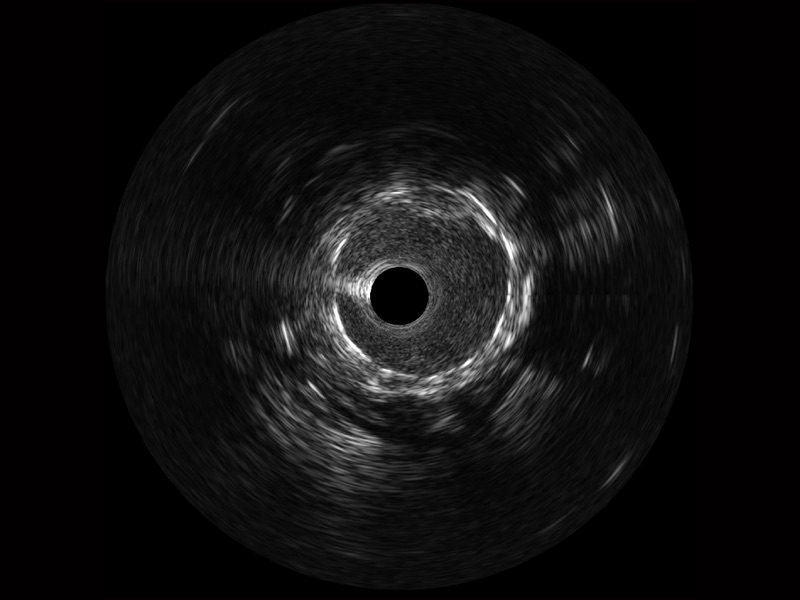

传统IVUS图像

对比传统IVUS导管成像,亚星官网宽频IVUS图像的近场支架梁显影更细腻,远场中膜外血管仍清晰可辨,兼顾远中近,兼顾分辨力与穿透深度